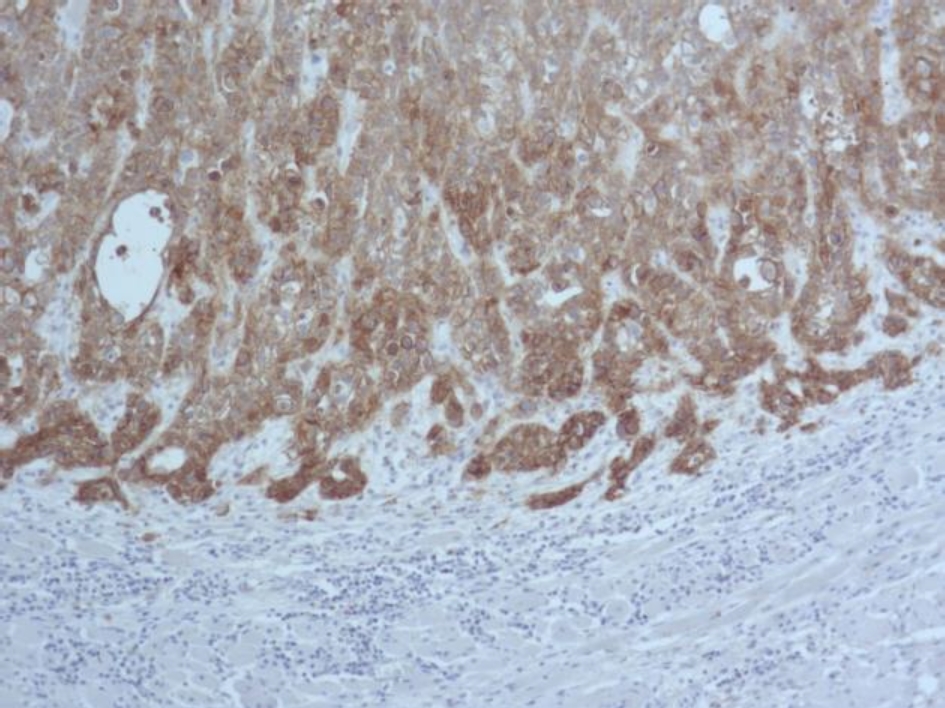

Во всех 19 исследуемых наблюдениях проведено дополнительное параллельное иммуногистохимическое исследование по выявлению экспрессии белков EGFR и Cyclin D1 соответственно, при этом диффузная, преимущественно умеренная экспрессия EGFR опреде-лялась в 17 (89 %) из 19 наблюдений (рис. 3), очаговая слабая экспрессия – в двух наблюдениях (11 %).

Экспрессия Cyclin D1 всех анализируемых наблюдений была очаговой, слабой и умеренной (рис. 4).

Рис. 3. Диффузная экспрессия EGFR в клетках плоскоклеточного рака языка. ИГХ окрашивание, ×100

Рис. 4. Очаговая слабая и умеренная экспрессия Cyclin D1 в клетках плоскоклеточного рака языка. ИГХ окрашивание, ×400

В нашем исследовании в 100 % наблюдений с амплификацией гена EGFR выявлена экспрессия белка EGFR, однако в 89 % экспрессия была сильной, а в 11 % наблюдений – умеренной. Исследователями также в 100 % наблюдений рака языка выявлено соответствие между амплификацией гена EGFR и экспрессией белка EGFR, однако наблюдения с высоким количеством копий EGFR сопровождались более интенсивной экспрессией белка EGFR при иммуногистохимическом исследовании. Мы не выявили такой закономерности.